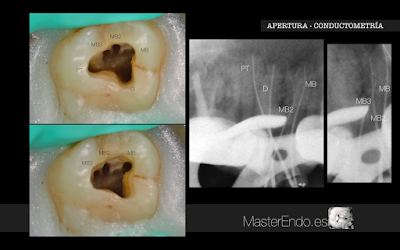

Apertura / Instrumentación:

Realizamos la apertura y localizamos los conductos mesial, distal y palatino. Se permeabilizaron mediante limas K#10. Una vez determinada la LT, trabajamos los conductos con proglider y el sistema Protaper Next hasta X2, y palatino hasta X3.

Con ayuda de microscopio, puntas ultrasónicas (START-X nº 2 y 3) se localizaron los conductos MB2 y MB3. Se permeabilizaron con limas K#6, 8, 10 y se instrumentaron con Proglider y Protaper Next hasta X2 a sus respectivas longitudes, confluyendo el conducto MB3 sobre MB2 a 12,5mm.